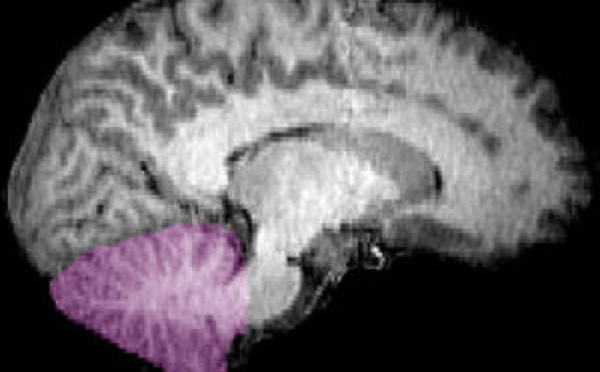

El extraño caso de la mujer de 24 años que vive sin cerebelo - 15/09/2014

Un equipo de médicos chinos ha diagnosticado a una mujer de 24 años de un raro trastorno conocido como como “agenesia cerebelosa”, que consiste en la ausencia total o parcial del cerebelo. A pesar de que esta área cerebral contiene la mitad de las neuronas del cerebro, la paciente muestra solo síntomas moderados (en forma de deficiencia motora y del habla), lo que, según los expertos, demuestra la enorme plasticidad de nuestra materia gris.